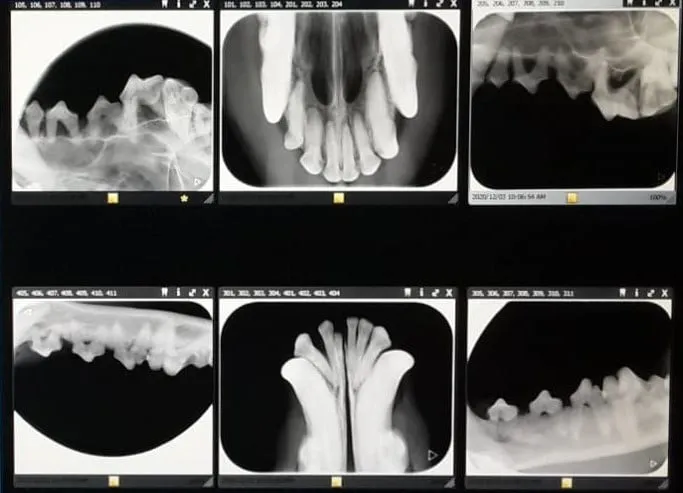

The clinic is deeply rooted in the local community, offering comprehensive veterinary care including orthopedic surgery, reproductive scans, artificial insemination, routine bird care, and herd health management for production animals. They also provide emergency care, diagnostic imaging like X-rays and ultrasounds, specialized surgeries, and tailored treatment plans for chronic conditions.

• Diagnostic imaging: X-rays, ultrasounds, and laboratory tests